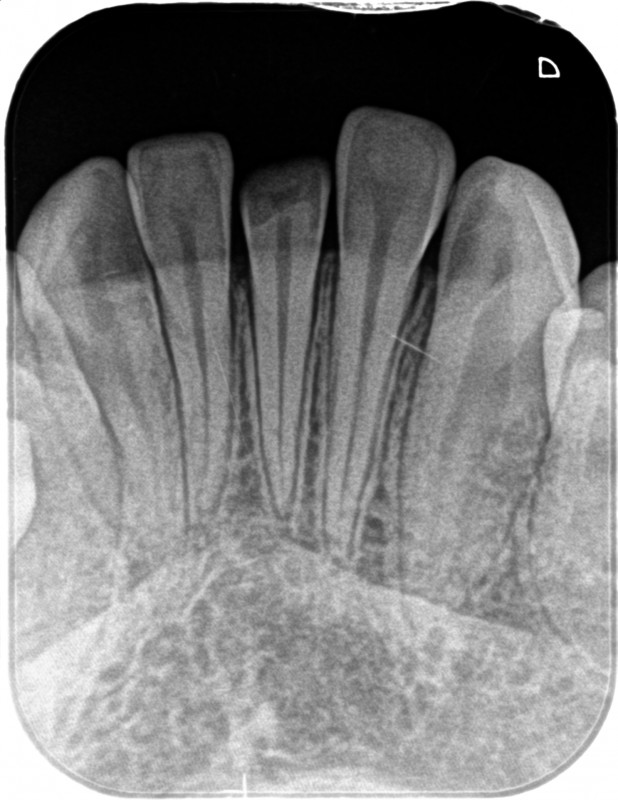

前歯が外傷で破折、神経が露出していたが、ダイレクトボンディングで修復したケース

前歯が外傷で破折、神経が露出していましたが、ダイレクトボンディングで修復したケースです。

このようなケース、一般的には神経を取ってかぶせ物を入れる治療になると思いますが、神経を取ると歯の寿命は短くなります。